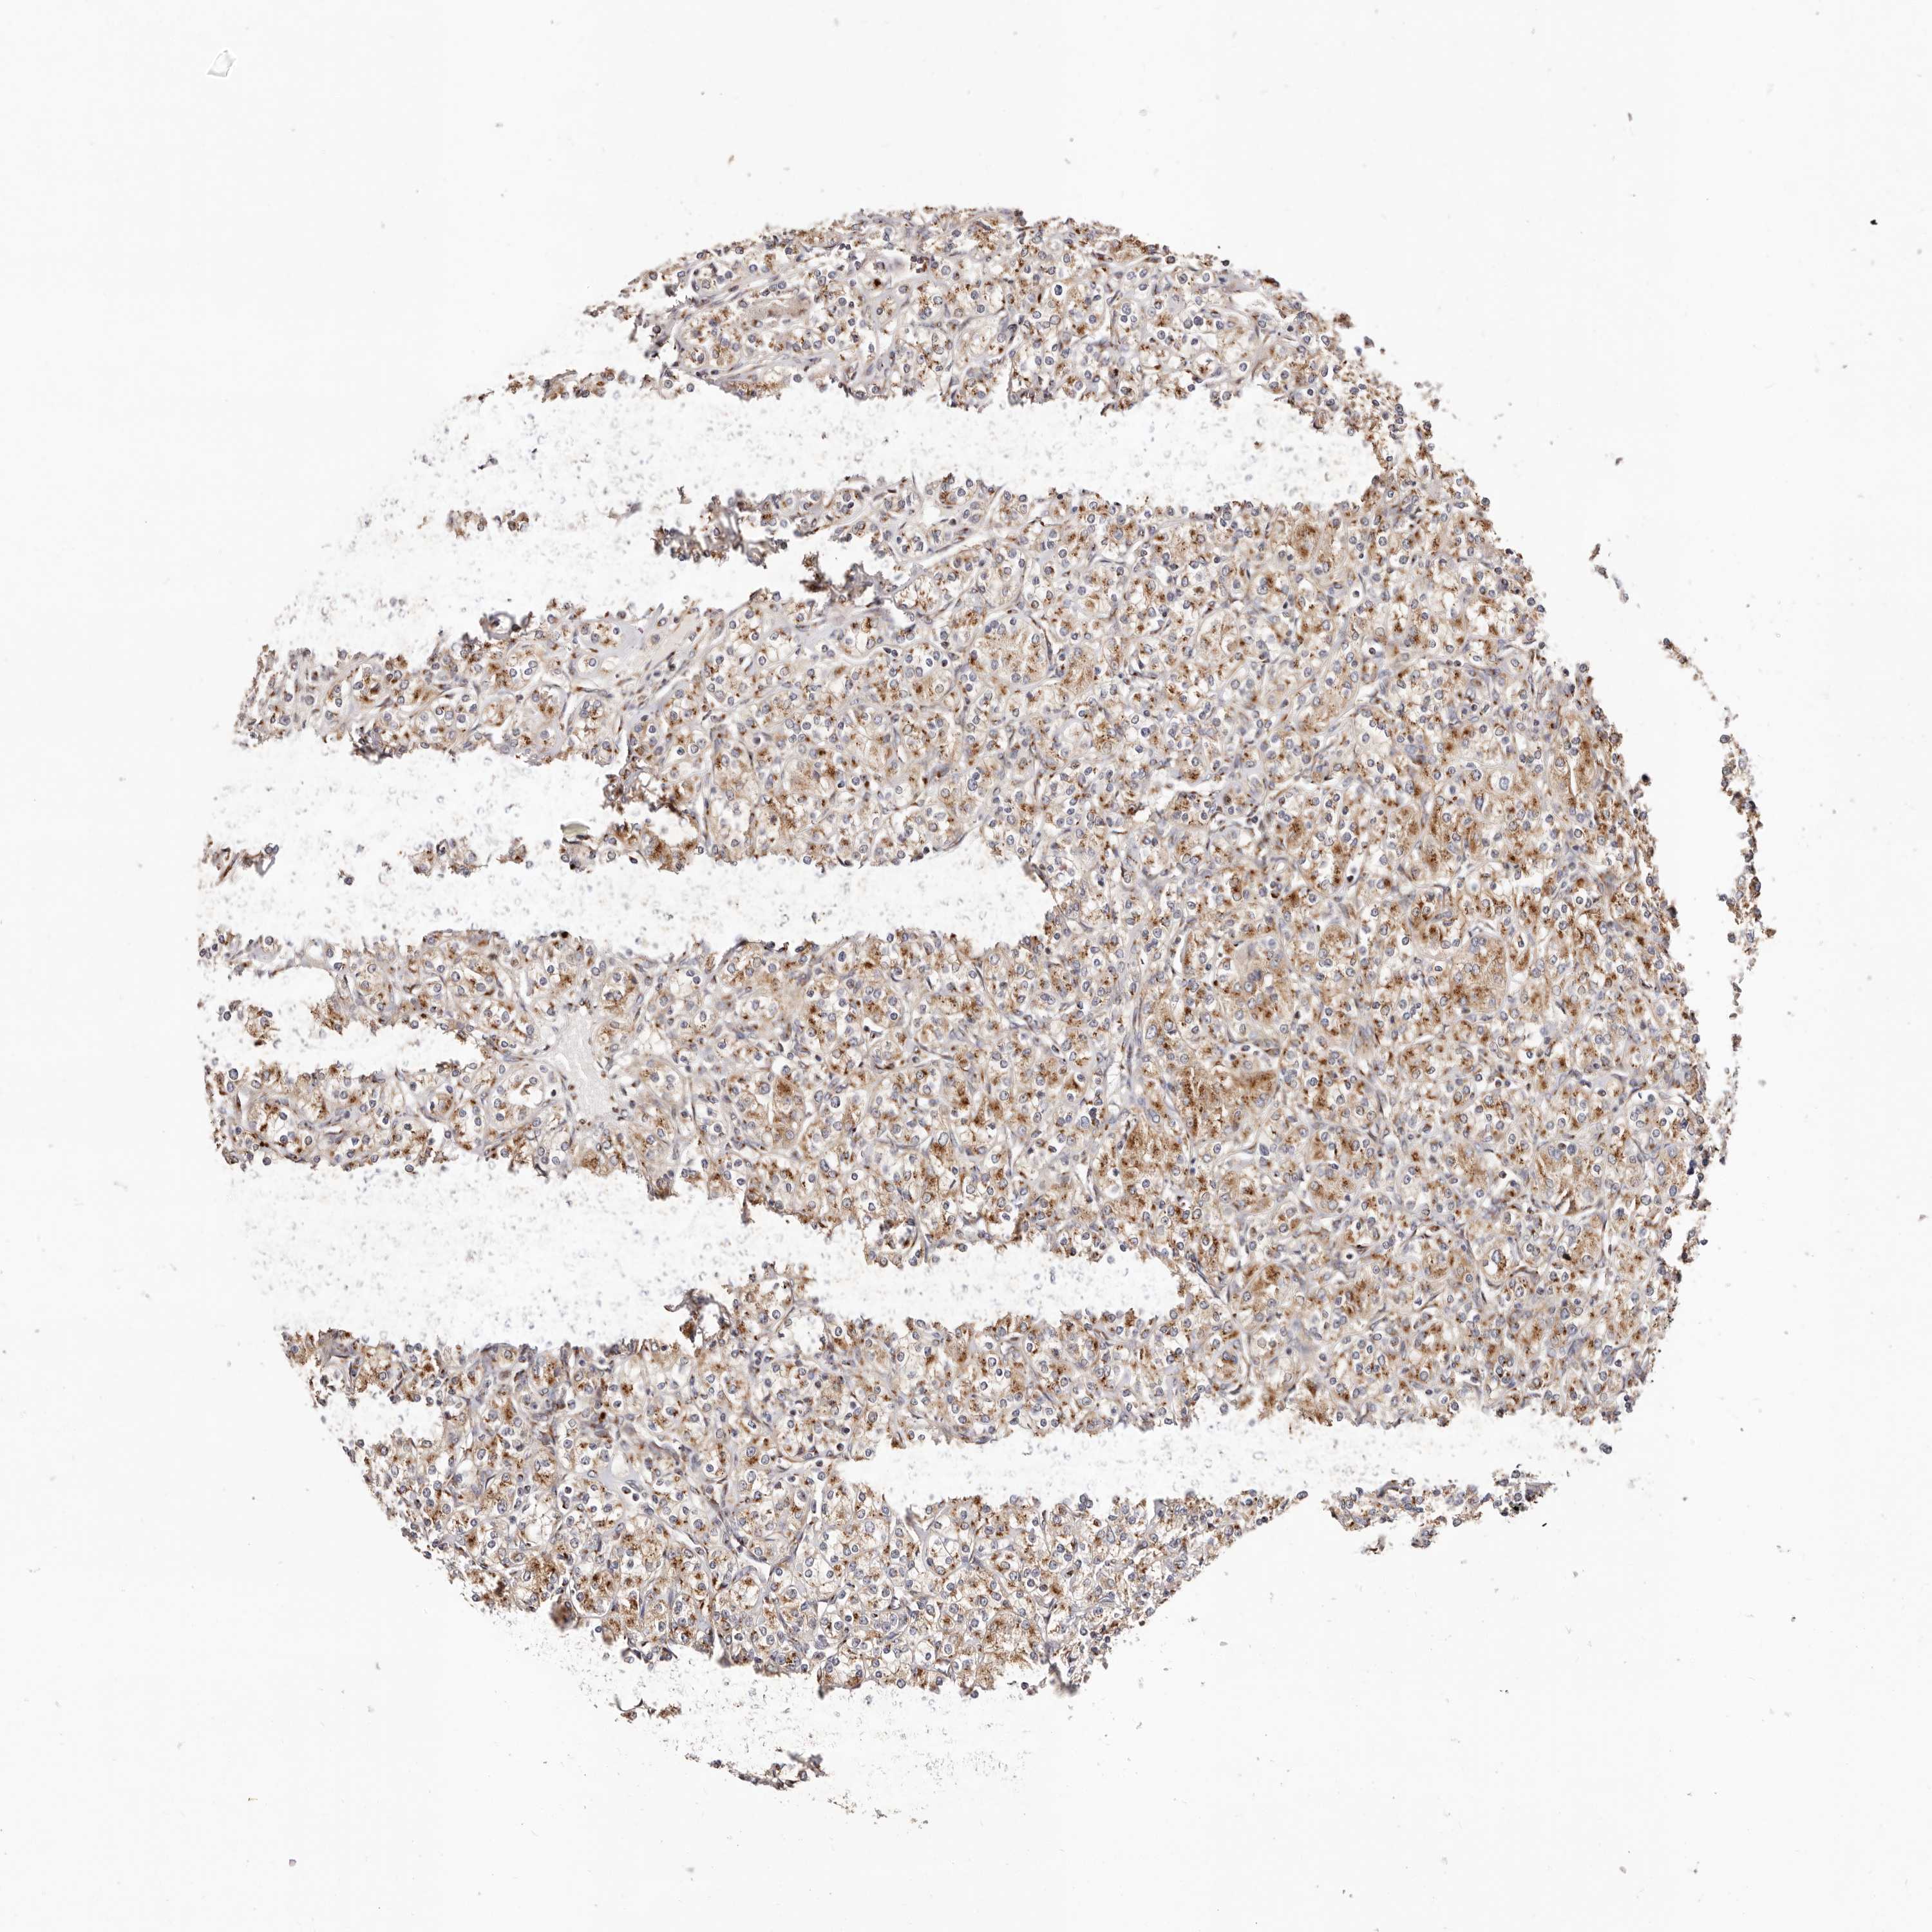

KIDNEY RENAL CLEAR CELL CARCINOMA (VALIDATION) - Interactive survival scatter ploti

The Survival Scatter plot shows the clinical status (i.e. dead or alive) for all individuals in the patient cohort, based on the same data that underlies the corresponding Kaplan-Meier plots. Patients that are alive at last time for follow-up are shown in blue and patients who have died during the study are shown in red.

The x-axis shows the expression levels (FPKM) of the investigated gene in the tumor tissue at the time of diagnosis. The y-axis shows the follow-up time after diagnosis (years). Both axes are complimented with kernel density curves demonstrating the data density over the axes. The top density plot shows the expression levels (FPKM) distribution among dead (red) and alive patients (blue). The right density plot shows the data density of the survived years of dead patients with high and low expression levels respectively, stratified using the cutoff indicated by the vertical dashed line through the Survival Scatter plot. This cutoff is automatically defined based on the FPKM cutoff that minimizes the p-score. The cutoff can be changed by dragging the vertical line or by entering a cutoff value in the square labeled "Current cut-off".

Under the Survival Scatter plot the p-score landscape (black curve; left axis) is shown together with dead median separation (red curve; right axis). Dead median separation is the difference in median mRNA expression between patients who have died with high and low expression, respectively. It is calculated as follows: median FPKM expression of dead patients with high expression - median FPKM expression of dead patients with low expression. This is intended to aid the user in visually exploring custom cutoffs and the associated p-scores and dead median separation.

Individual patient data is displayed and can be filtered by clicking on one or more of the category buttons on the top of the page. Categories describing expression level and patient information include: high, low, alive, dead, female, male and tumor stages. The scale of the x-axis can be toggled between linear and log-scale by clicking on the "x log" button. Mouse-over function shows TCGA ID, patient information and mRNA expression (FPKM) for each patient.

& Survival analysisi

Kaplan-Meier plots summarize results from analysis of correlation between mRNA expression level and patient survival. Patients were divided based on level of expression into one of the two groups "low" (under cut off) or "high" (over cut off). X-axis shows time for survival (years) and y-axis shows the probability of survival, where 1.0 corresponds to 100 percent.

MAPK6 is not prognostic in Kidney Renal Clear Cell Carcinoma (validation)

Best expression cut offi

Based on the FPKM value of each gene, patients were classified into two groups and association between prognosis (survival) and gene expression (FPKM) was examined. The best expression cut-off refers the FPKM value that yields maximal difference with regard to survival between the two groups at the lowest log-rank P-value. Best expression cut-off was selected based on survival analysis .

When clicking on this number, the vertical dashed line indicating cut-off, the interactive survival plot, and the Kaplan-Meier curve will be adjusted to show results based on the best expression cut-off.

: 15.27

Median expressioni

Median expression refers to the median FPKM value calculated based on the gene expression (FPKM) data from all patients in this dataset. When clicking on this number, the vertical dashed line indicating cut-off, the interactive survival plot, and the Kaplan-Meier curve will be adjusted to show results based on the median expression.

: N/A

Median follow up timei

Median follow up time refers to the median time (years) after diagnosis with this type of cancer, based on clinical data from all patients in this dataset.

P scorei

Log-rank P value for Kaplan-Meier plot showing results from analysis of correlation between mRNA expression level and patient survival.

N/A

5-year survival highi

5-year survival for patients with higher expression than the expression cutoff.

For melanoma and glioma, 3-year survival is shown.

5-year survival lowi

5-year survival for patients with lower expression than the expression cutoff.

TCGA RNA samplesi

RNA-seq data is reported as average FPKM (number Fragments Per Kilobase of exon per Million reads), generated by the The Cancer Genome Atlas (TCGA) .

Normal distribution across the dataset is visualized with box plots, shown as median and 25th and 75th percentiles. Points are displayed as outliers if they are above or below 1.5 times the interquartile range. FPKM values of the individual samples are presented next to the box plot.

Average pTPM 16.7

Number of samples 100